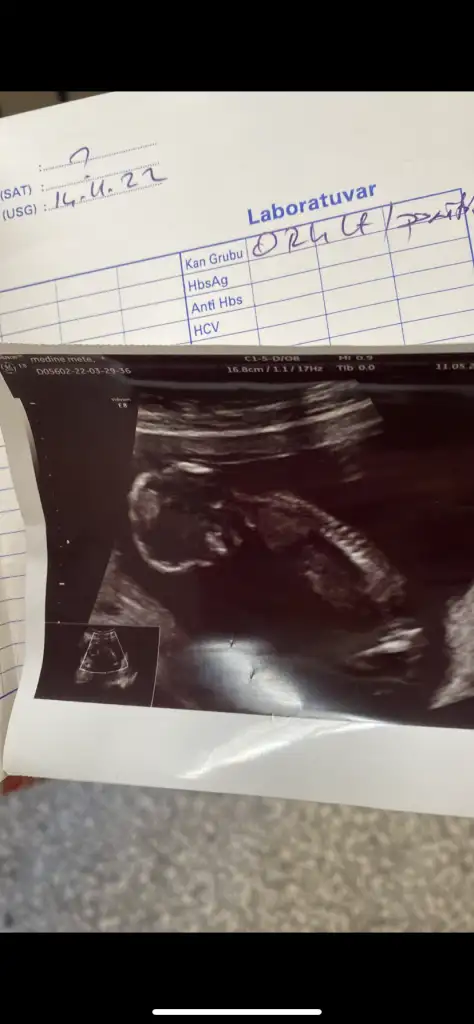

merahaba 11+3 karnımdan bakıldıSelam Kızlarbir çok kişi gruplardan beni bilir. Yine yetiştim imdatlara

Merhaba :) bana 6.haftada erkek demiştiniz. Doktor da 12+3te erkek gibi dedi, tekrar bakabilir misiniz :)Hala kız gibi duruyorhadi bakalım inşallah kalbinden ne geçiyorsa o olur

O pipi gibi ama altındaki paralel olan şey neterzi söküğünü dikemez hesabı ben bir şey diyemiyorum bakın sizce bu yatay duran pipimi![]()